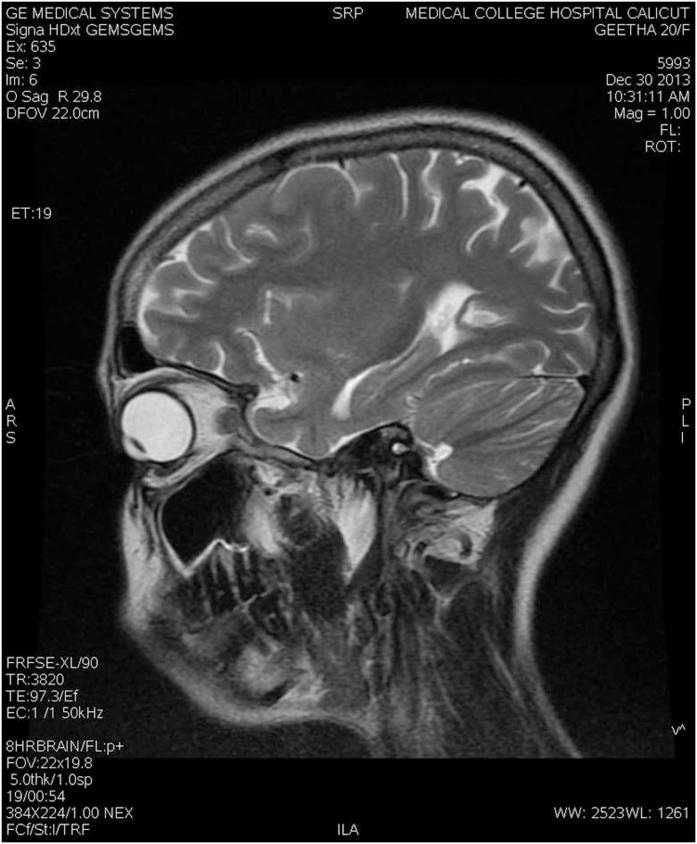

双侧原发性视神经病变作为免疫功能正常患者结核病的首发表现。

Bilateral primary optic neuropathy as the presenting manifestation of tuberculosis in an immunocompetent patient.

Vision impairment is one of the devastating complications of central nervous system tuberculosis (CNS TB). Optic atrophy is a sequelae of various forms of CNS TB which, ultimately, is responsible for vision impairment. It is usually the secondary optic atrophy which occurs in CNS TB. In this case report, we present the story of an immunocompetent woman presenting as bilateral visual loss. She was found to have primary optic atrophy. Neuroimaging revealed features of chronic meningitis. Polymerase chain reaction test for Mycobacterium was positive in cerebrospinal fluid. Although secondary optic atrophy is common in the CNS TB, as a complication of meningitis, primary optic atrophy per se is infrequently reported.

摘要

视力损害是中枢神经系统结核(CNS TB)的严重并发症之一。视神经萎缩是各种形式的CNS TB的后遗症,最终导致视力损害。在CNS TB中通常发生的是继发性视神经萎缩。在本病例报告中,我们讲述了一名免疫功能正常的女性出现双侧视力丧失的故事。她被发现患有原发性视神经萎缩。神经影像学显示慢性脑膜炎的特征。脑脊液中结核分枝杆菌的聚合酶链反应检测呈阳性。虽然继发性视神经萎缩在CNS TB中很常见,是脑膜炎的并发症,但原发性视神经萎缩本身很少被报道。